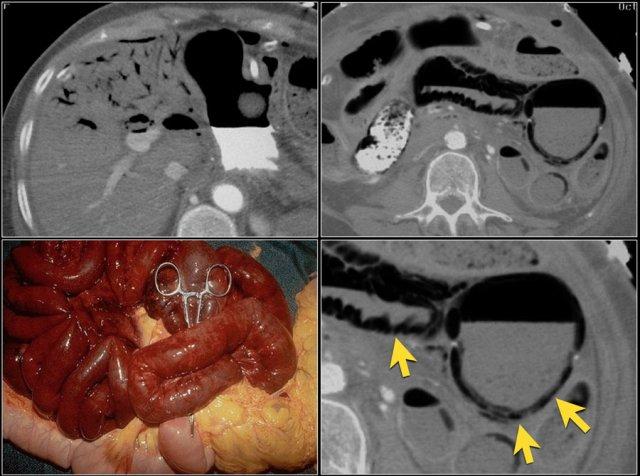

Các hình ảnh này thuộc về bệnh nhân bị tắc ruột non dạng quai kín.

Lưu ý nhóm các quai ruột non có thành dày ở vùng bụng trên phải (mũi tên vàng).

Phù nề mạc treo ruột (mũi tên đỏ) cho thấy tình trạng tăng áp lực tĩnh mạch do thắt nghẹt.

Giãn mạch máu

Tăng áp lực tĩnh mạch trong thắt nghẹt cũng dẫn đến giãn tĩnh mạch (mũi tên vàng).

Bệnh nhân này cũng có tắc ruột dạng quai kín với kiểu ngấm thuốc xám của các quai ruột bị thắt nghẹt (mũi tên đỏ).

Lưu ý sự ngấm thuốc bình thường của ruột non ở phía trên vị trí tắc nghẽn (mũi tên xanh lá).

Một bệnh nhân khác với hình ảnh ruột thiếu máu cục bộ và phù nề mạc treo ruột lan rộng.

Trong phẫu thuật, toàn bộ đoạn ruột non này đã bị hoại tử.